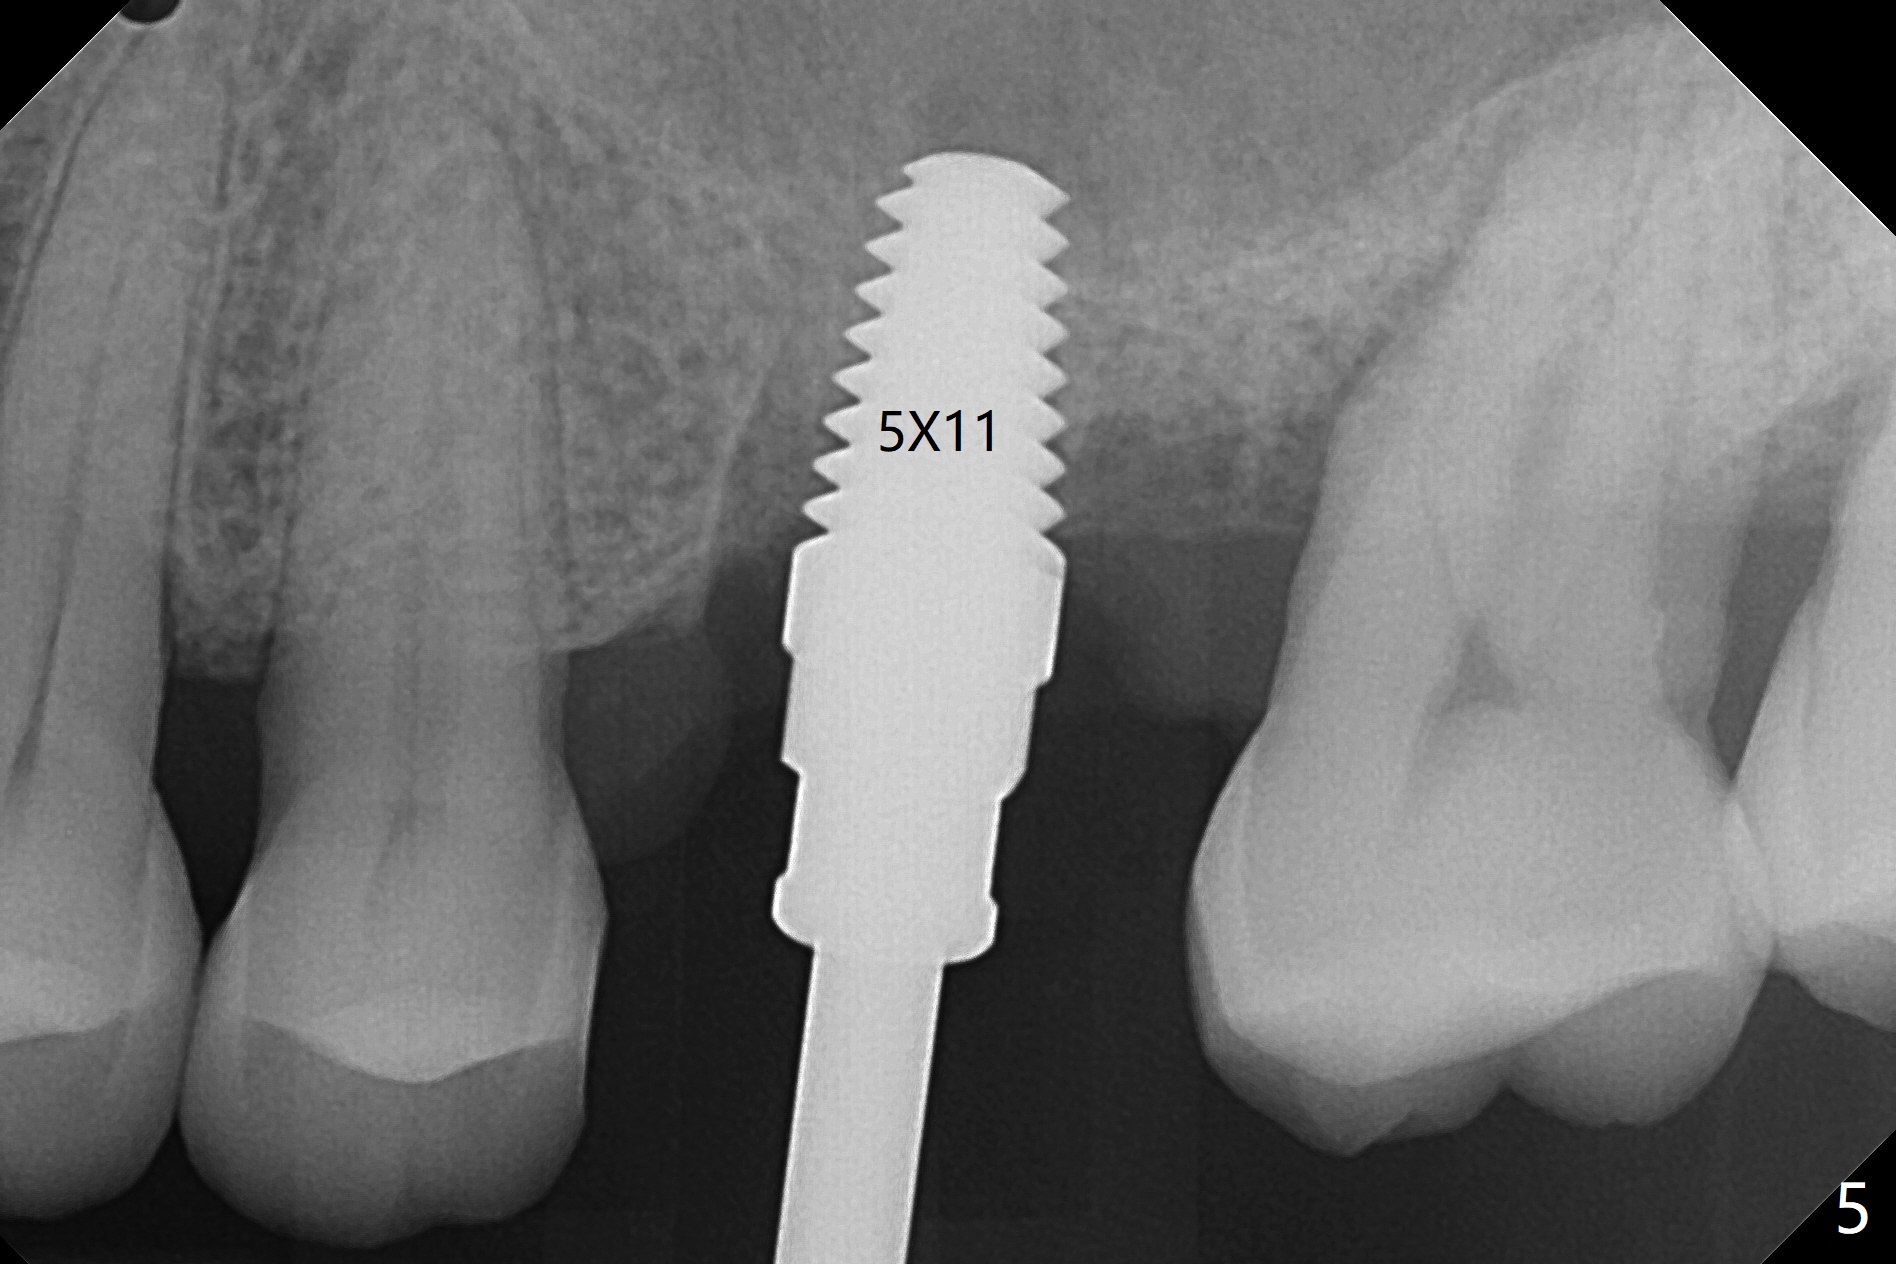

A 65-year-old man had crack tooth syndrome at #14 one month earlier (Fig.1). He shows up with crack and pain in an emergency manner (Fig.2 arrowheads). Preop CT confirms 4.5 mm bone height (Fig.3). Osteotomy will be initiated in the middle of the septum between 3 sockets (Fig.4). Depth of osteotomy is controlled with drill stoppers. After sequential osteotomy free hand, a 5x11 mm tap is used to break through the sinus floor (Fig.5) and sinus lift with Vanilla allograft. To prevent abutment screw loosening, a 5x11 mm tissue-level implant is placed; the distal thread is equicrestal (Fig.6 arrowhead). Following deeper placement of the implant (Fig.7 arrow) with a larger and longer abutment (as compared to that in Fig.6), the margin for an immediate provisional (Fig.9 white curved lines) is prepared in the coronal end of the implant (Fig.8 between arrowheads). With the tissue-level implant, the crown/implant ratio improves. Stress will be partially acting on the implant so that there is less likelihood of abutment screw loosening. The socket heals 1 month postop (Fig.10). The rough surface of the implant is exposed ~ 1 mm. With the margin modified and polished, the provisional returns to place with oral hygiene instruction. It is hoped that the gingiva will cover the exposed rough surface. The buccal rough surface remains exposed 5 months postop (Fig.11). The bone in sinus lift is mature 5 months postop (Fig.12,13). The first 1-2 implant threads are expected to be filled with mature bone in the near future (*). Since the abutment seems long enough for retention, temp bond is used for cementation (Fig.14). Water pik is being applied.